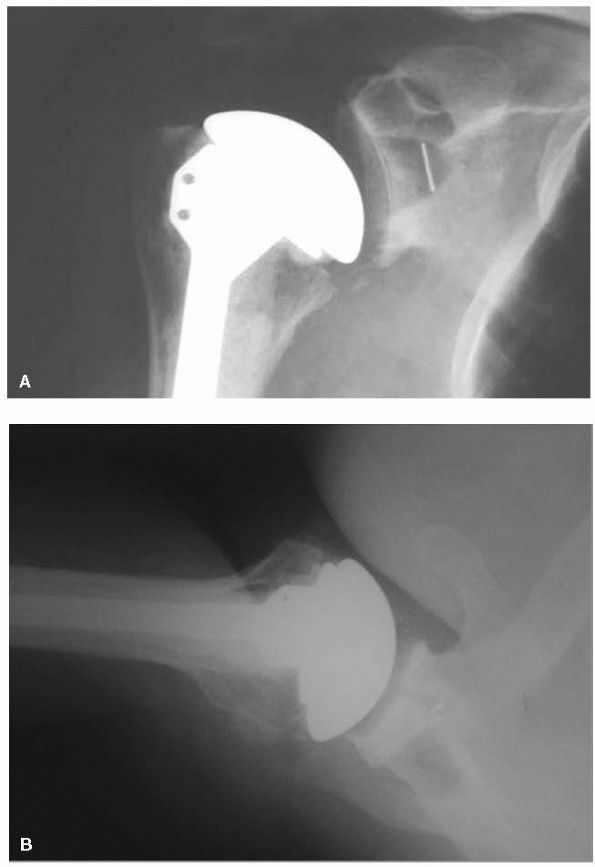

![]() |

FIGURE 12-10. Total shoulder arthroplasty. (A) Anteroposterior and (B) axillary radiographs of a total shoulder prosthesis.